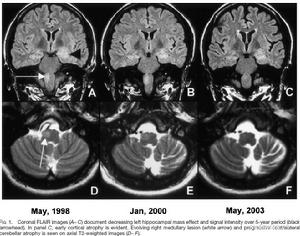

橄欖橋腦小腦萎縮錐體束征。本組有8例行CT檢查未發現異常,但頭顱MRI見小腦橋腦萎縮,所以MRI檢查是有價值的輔助診斷方法。